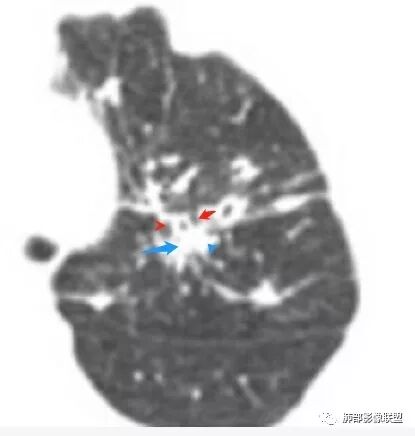

薄壁空洞,壁光滑,稍厚

双侧对比中央间质增厚

多发结节、斑片,大树芽征,沿支气管血管束分布

这些是支气管壁增厚为主

这些我觉得血管增粗比支气管还厉害